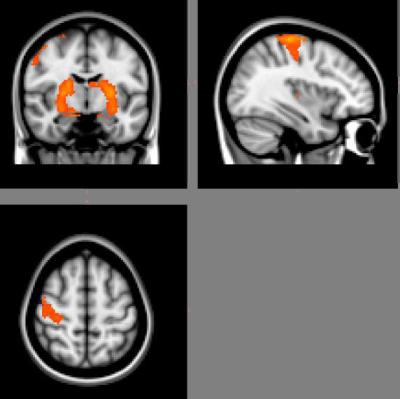

image: These figures correlate fMRI activation with how finger sequences are grouped into integrated clusters. This leads to the the production of fluid low-cost movements. view more

Researchers collected brain imaging data from people performing a motor task, and then analyzed this data using new computational techniques. They found evidence that the flexibility of a person's brain can be used to predict how well someone will learn. The researchers view flexibility as how different areas of the brain link up in different combinations.

"Parts of the brain communicate with one another very strongly, so they form a sort of module of intercommunicating regions of the brain," said first author Danielle S. Bassett, postdoctoral fellow in physics at UCSB. "In this way, brain activity can segregate into multiple functional modules. What we wanted to measure is how fluid those modules are."

Bassett explained that there are flexible brain regions with allegiances that change through time. "That flexibility seems to be the factor that predicts learning," said Bassett. "So, if you are very flexible, then you will end up learning better on the second day, and if you are not very flexible, then you learn less."